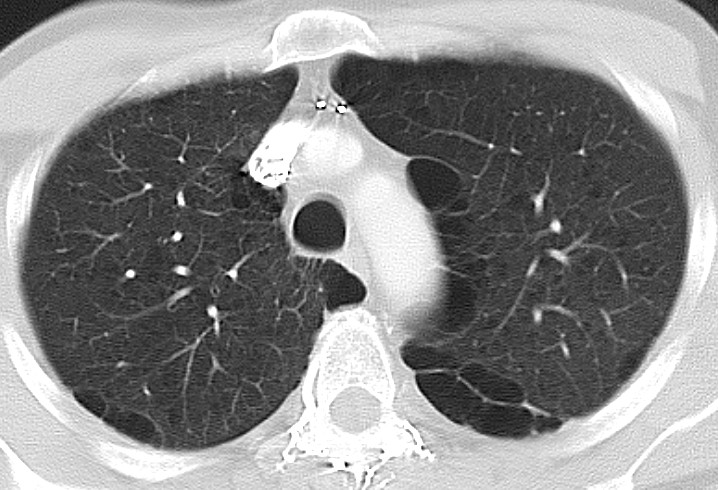

Множественные БУЛЛЫ В ЛЕГКИХ на КТ РАСШИФРОВКЕ и подозрение на синдром Маклеода

ХОБЛ - эмфизема легких на КТ заключении грудной клетки (КТ второе мнение)